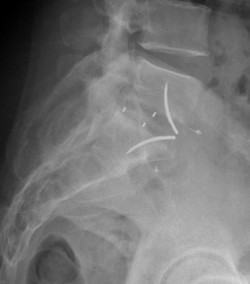

Cage vue de profil

La cage intervertébrale en place

Radiographie de profil